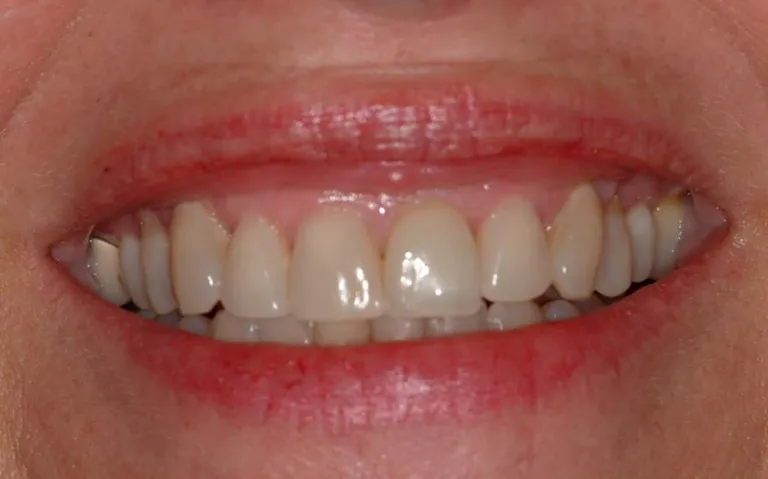

Antes y después de implante único